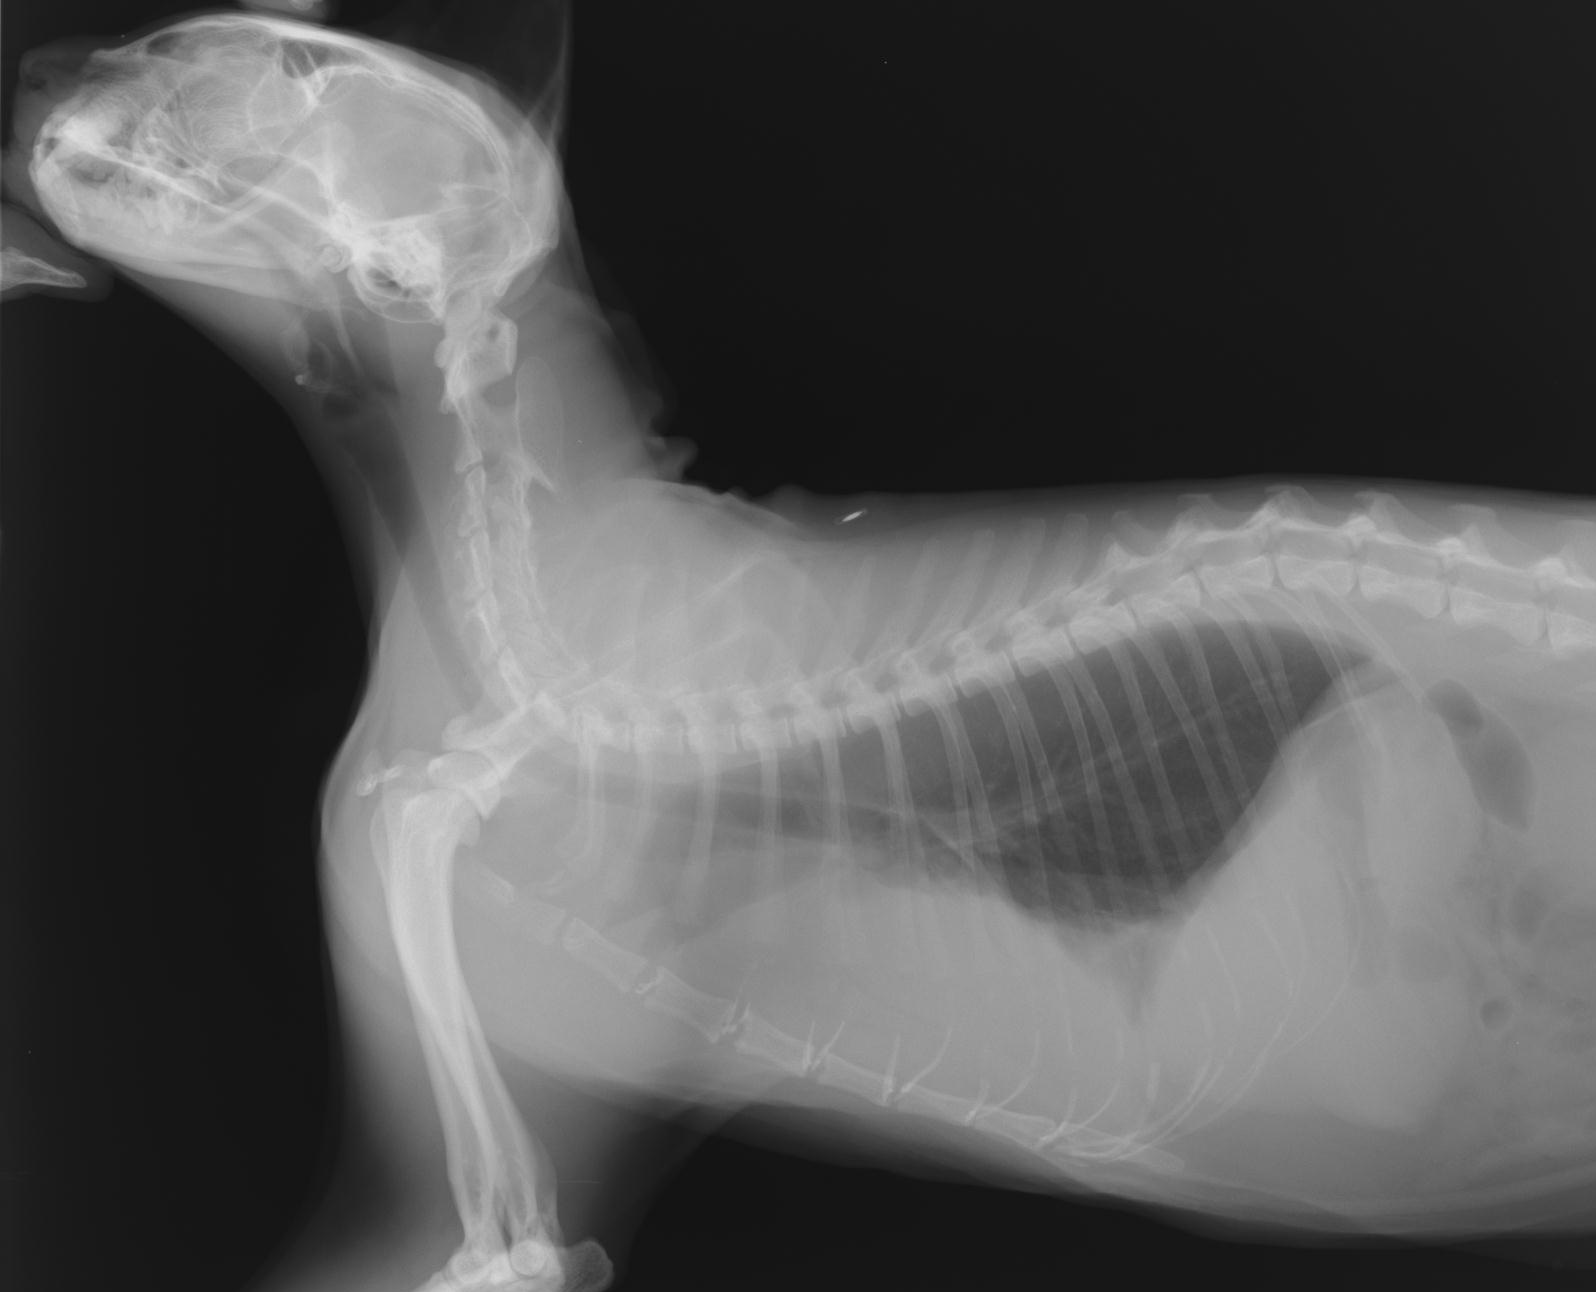

レントゲン検査

通常見ることのできない内臓の大きさや形、配置の変化を調べます。

心臓病、肺や気管・気管支の状態、腹腔内諸臓器の大きさや形の変化、腫瘍や結石の有無などがわかります。

肥大型心筋症・動脈血栓塞栓症

猫・中年齢以降で見られ、心臓の壁が分厚くなってしまう病気です。この病気は、だいぶ進んで、突然、後肢を引きずり、ギャアギャア泣き喚くなどの症状を呈して初めて気づくこともあります。こういった症状を呈する前に検診でそのリスクを発見することもできます。

若い年齢から検診で心雑音を発見することがあり、のちのち心臓病に繋がることもしばしばあります。